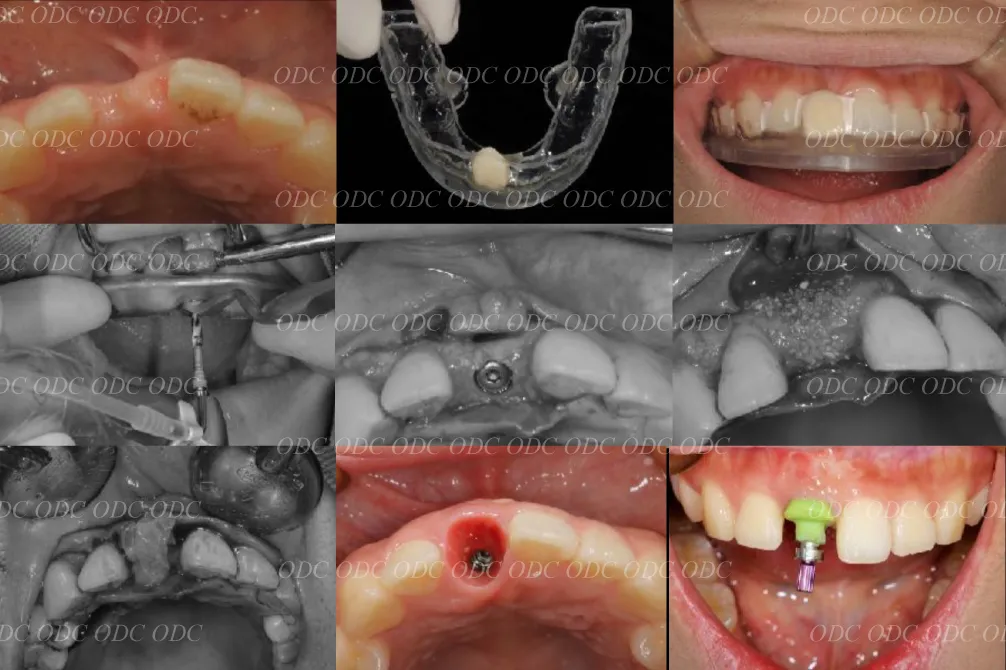

前歯部少数歯欠損症例

2014年、前歯1本欠損でインプラント治療を希望されて来院されました。

サージカルガイドを作成しインプラント埋入を行っていきました。

※ 詳細のステップをご覧になりたい方はこちらをご覧ください。

骨造成 結合組織移植等を行いながら最終印象を行っていきました。

最終補綴装着後の口腔内写真です。自然な仕上がりにご満足頂いております。